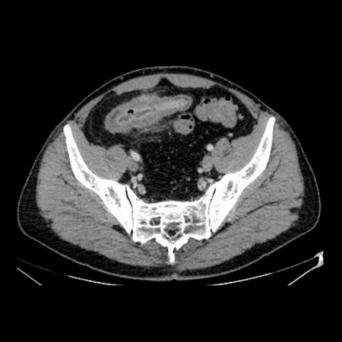

Le cancer du sein est le cancer le plus fréquent chez la femme dans le monde, avec environ 61 000 nouveaux cas annuels estimés en France. Au cours des dernières années, nous avons assisté à des améliorations majeures, allant du dépistage au traitement.